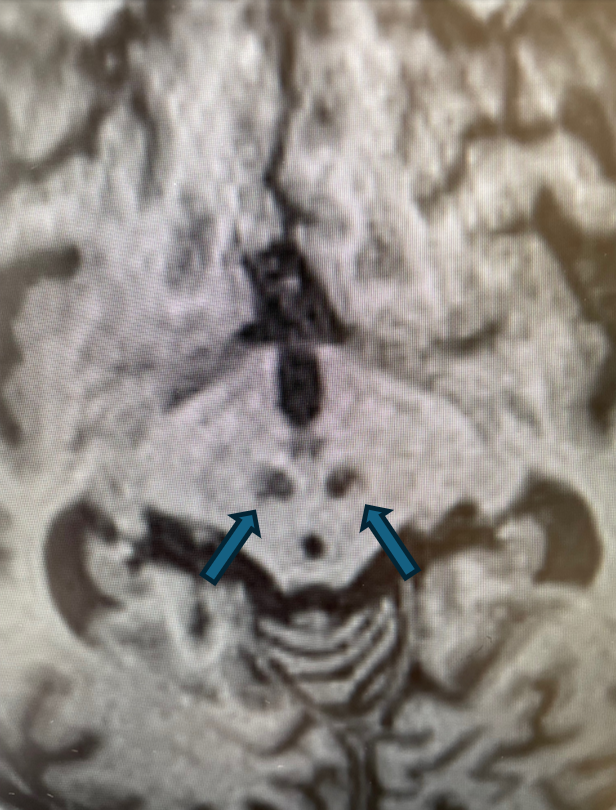

Rycina 3. Cechy akumulacji jonów żelaza w obrębie jąder czerwiennych. (T1).

rycinka